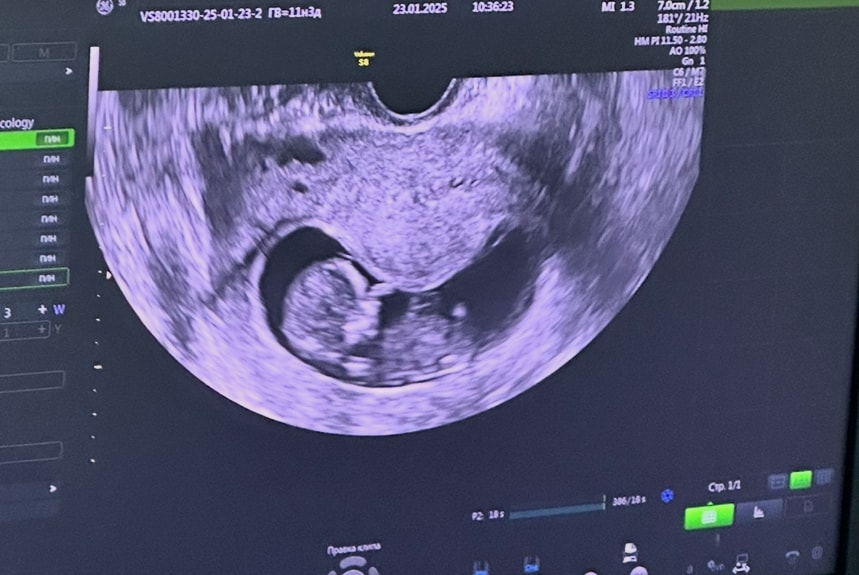

Изображение

Счастье, вот в 9-10 недель. Я думала его там вообще сдавило. Оказывается это только так выглядит. Врач сказала все хорошо

Счастье, вот и мне его перестали мерить. Но когда смотрю чужие узи, там прям место полно в плодном яйце, а у меня чуть ли не в облипку оно стало последний раз, вообще без понятия как он будет там переворачиваться, вот и волнуюсь